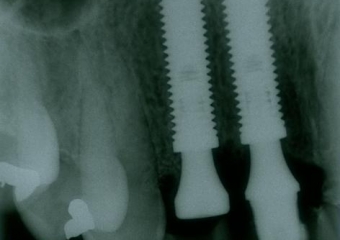

Rx dos implantes Cone Morse instalados